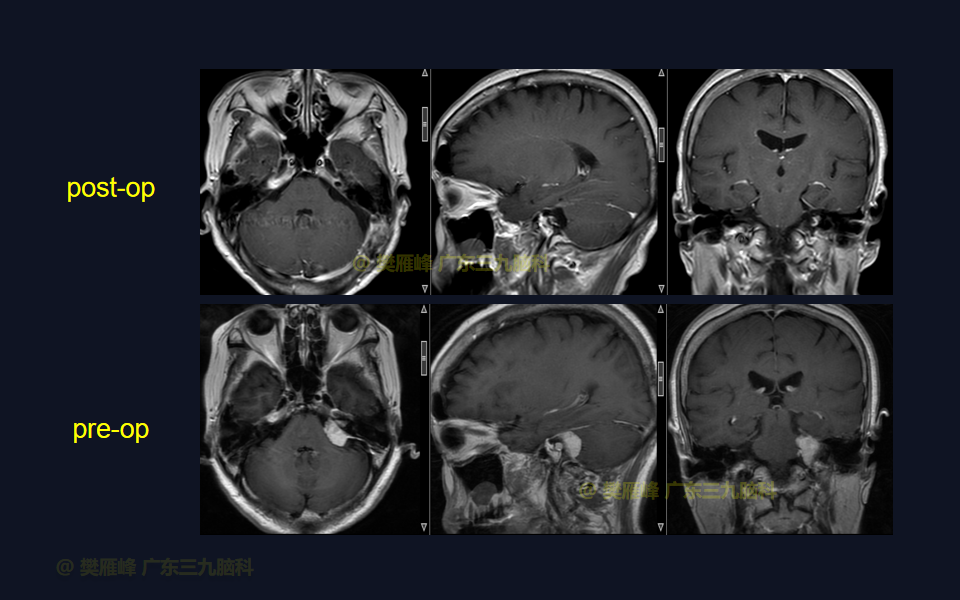

在这个二维手术视频中,展示了经枕下乙状窦后入路切除侵入内听道的桥小脑角脑膜瘤的方法。患者是一名66岁的女性,有2年左耳耳鸣伴听力下降,突发头晕半月,无面瘫病史,神经影像学显示左侧桥小脑角的侵入内听道从脑膜瘤。他接受了经乙状窦后入路保留面听神经的方法,术中肿瘤与脑干和面听神经轻度粘连,完全切除肿瘤。术后无面瘫,听力较术前明显改善,神经影像学显示肿瘤完全切除。我们展示了安全的颅神经和肿瘤切除术的细微差别和技术要点。

在这段手术视频中,展示了一名66岁女性的病例,他因左耳耳鸣伴听力下降2年余,突发头晕半月发现的左侧桥小脑角区脑膜瘤